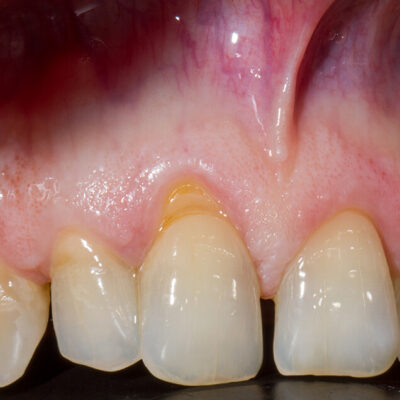

Esempio di recessione gengivale

Recessione Gengivale

La recessione gengivale è una patologia dentale che riguarda il ritiro della gengiva verso il margine apicale del dente, la zona che corrisponde alla radice del dente.

Questa situazione, oltre ad essere esteticamente disturbante, può portare ad avere ulteriori disagi, come ipersensibilità dentale, infiammazione e formazione di carie sulla radice che si scopre. Visivamente la recessione gengivale si presenta con la forma più allungata dei denti, proprio a causa del ritiro della gengiva che scopre parte della radice.

Canino superiore con recessione: prima e dopo Intervento di Chirurgia Mucogengivale con sostituti dermici

Quando le recessioni sono iniziali è sufficiente modificare le tecniche di spazzolamento e tenere le lesioni sotto controllo.

Quando iniziano a diventare un problema estetico, soprattutto nei denti anteriori , quando il paziente accusa molta sensibilità o i denti tendono a cariarsi sulla porzione di radice scoperta la Chirurgia Mucogengivale è in grado di riportare le gengive a dei livelli corretti.

La tecnica chirurgica prevede spesso il prelievo di una porzione di mucosa prelevata dal palato che andrà inserita nella zona della recessione gengivali. Questo normalmente causa un notevole fastidio al paziente nella zona di prelievo dal palato.

Da più di 15 anni la ricerca sui biomateriali ha messo a disposizione degli ottimi sostituti connettivali che evitano il prelievo di connettivo dal palato.

Per il trattamento chirurgico di circa 1.500 recessioni gengivali il dr. Patarino Domenico ha sempre utilizzato i biomateriali sostituti dermici, evitando il prelievo dal palato, con ottimi risultati clinici, evitando le complicanze possibili di questo intervento e diminuendo di molto il dolore e il gonfiore post-operatorio dei suoi pazienti.